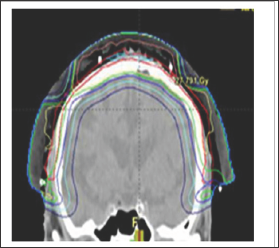

b) The use of computer tomography (CT) planning scans. MVT enables the use of computer tomography (CT) planning scans taken in the treatment position, and planning systems. The volumes to be treated and avoided are contoured by the radiation oncologist on these scans. Doses are prescribed for each volume. Dose Volume Histograms (DVHs) can be constructed and doses per volume on each individual patient plan can be compared to standardized doses for CTV and PTV and OARs. These standardized doses are known to predict cure for tumour bearing volumes and are associated with acceptable side effects in normal tissue volumes. Technology with the planning system is then used to optimize the plan to achieve these bench marks, ensuring tumour cure and normal tissue tolerance at the end of treatment (Figure 9).

Figure 9: Photographs and CT plans of a patient preparing for VMAT.

A: Mark up of a scalp field at planning showing areas of gross tumour within the area of ESFC.

B: CTV is contoured on the planning scan. Red volume represents ESFC.

C: The resultant dosimetry avoiding brain. The dose homogeneity is uniform throughout the target. The dose profile across the field is uniform with no need for junctioning radiation fields. Green volume represents gross tumour.

C)The use of Intensity modulated radiotherapy (IMRT). IMRT, using automated multileaf collimators in the head of the linac, enables the intensity of the beam to be modified during beam-on time, sculpting the dose to the contoured volumes. Prior to this advance radiotherapy was initially Two Dimensional (2D) and based on fields. The application of CT technology in planning accelerated the uptake of progression to Three Dimensional Conformal Radiotherapy (3DCRT) with the concept of volume treatment. However, RT still came in "blocks" IMRT allowedtreatment around curves, especially sparing dose to OARs in the concavity of a volume requiring treatment (e.g. brain underneath a scalp)

The significance of these advantages for skin cancer is that radiotherapy can now treat large curved convex surfaces, such as those found in ESFC. Large convex surfaces of ESFC can be found covering anatomical sites such as the scalp, forehead, cheeks, forearms, legs, chest, upper back, and shoulders, VMAT can now be used to treat these skin surfaces with definitive MVT photon RT (Figure 9). These advances have overcome the problems of traditional RT. The dose can now be more uniform throughout the target, with no need for junctioning radiation fields.